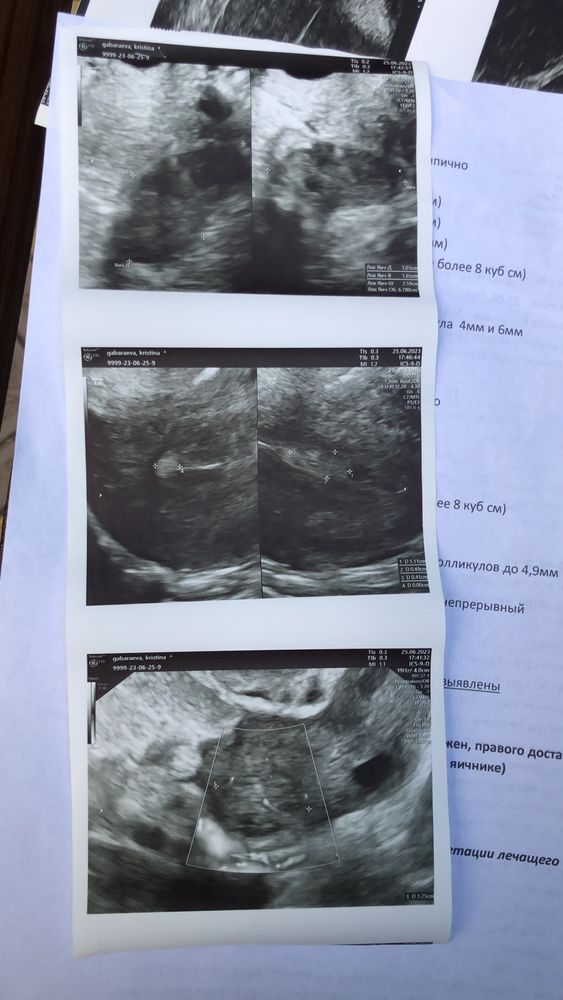

Фолликулометрия

Елена Л, все пойду к врачу обязательно 🙏🏻😍 я сегодня так обрадовалась ..на узи сказали что все отлично..и овуляция появилась .. ее не было почти пол года.. в ноябре была зб после этого не было ((( но теперь я такая радостная .. это ещё мы на эко собрали документы.. дай Бог не понадобится 🙏🏻